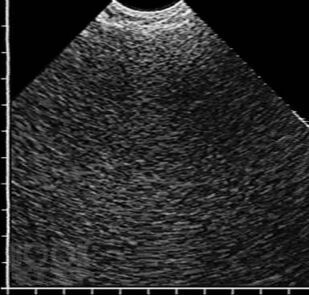

В учебном пособии в практическом аспекте изложены вопросы ультразвуковой диагностики воспалительных заболеваний легких: приведены методика исследования и нормальная эхографическая картина грудной клетки, подробно освещены ультразвуковая семиотика и дифференциальная диагностика пневмоний, в том числе деструктивных, абсцессов и гангрены легкого, для каждого из них выделены диагностически значимые эхопризнаки. Впервые представлена эхосемиотика пневмоний в зависимости от степени тяжести воспалительной инфильтрации, а также абсцессов легкого в зависимости от эффективности спонтанного дренирования его полости бронхами. Пособие иллюстрировано большим количеством эхограмм, отображающих основные диагностические признаки рассматриваемых заболеваний.